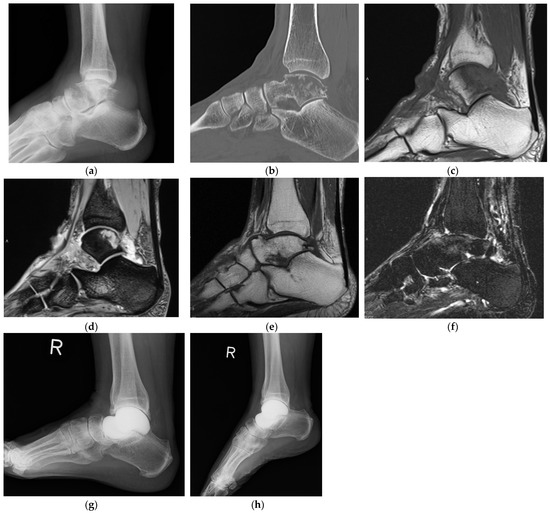

- Yang, Q.D.; Mu, M.D.; Tao, X.; Tang, K.L. Three-dimensional printed talar prosthesis with biological function for giant cell tumor of the talus: A case report and review of the literature. World J. Clin. Cases 2021, 9, 3147–3156. [Google Scholar] [CrossRef] [PubMed]

| Yang 2021 [24] | Case report | 22 | M | GCTB | Talar prosthesis | Talectomy and total talar prosthesis (ocrmo material, constrained) |

| Yang 2021 [24] | 25 | 89 | NR | 0 | None | CDF | 1 |